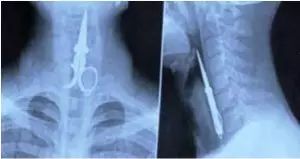

1.这个哥们儿在洗牙时,因为朋友讲的笑话太好笑,把一把剪刀吞了下去……

这个哥们儿在洗牙时,因为朋友讲的笑话太好笑,把一把剪刀吞了下去